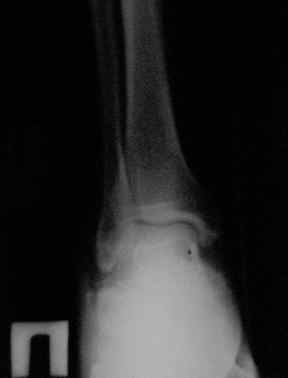

Уважаемый Дмитрий! Можете ли Вы добавить аксиальные проекции!

Присоединяюсь к мнению Я.Одесского о необходимости аксиальных снимков и, наверное, сразу снимков по Бродену (через каждые 10 градусов внутренней ротации стопы). Кроме этого необходима КТ. Она позволит уточнить срослись переломы или нет. Соответственно и тактика: если не срослись можно попробовать АВФ; если срослись -артродез.

С левой стопой дело похуже. Нужен прямой снимок, да и боковой не помешает повторить на всю стопу, ну и плюс аксиальный. Готовтье аппарат.

Отправляю снимки(свежие)и фото стоп.

С уважениемД.Б.